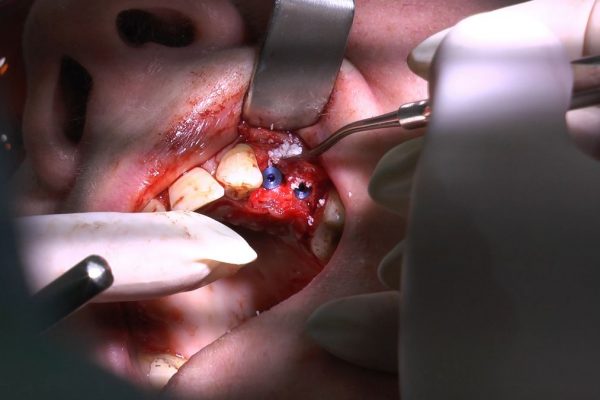

W ostatni weekend czerwca 2018 roku kursanci II Sezonu Preludium Implantologii odbyli piątą, finałową sesję, która w całości podporządkowana była praktyce. W ciągu dwóch dni zabiegowych Lekarze uczestniczący w szkoleniu przeprowadzili szereg zabiegów pod kierunkiem dr n.med. Violetty Szycik. Wszczepili 17 implantów oraz przeprowadzili ekstrakcje i zabiegi regeneracyjne kości. Zabiegi były wykonywane także w sedacji dożylnej z udziałem specjalisty anestezjologii i intensywnej terapii dr Jolanty Grzybowskiej. Preludium implantologii to nowy program edukacyjny dla adeptów implantologii stomatologicznej, którego celem jest wprowadzenie do implantologii poprzez pozyskanie wiedzy w szerokim zakresie i uwzględnieniem szczegółów mających decydujące znaczenie dla powodzenia leczenia implantologicznego. Ale tak jak wszystkie szkolenia w Instytucie Vivadental, w tym wiodące Practiculum Implantologii, zorientowane jest na praktyce i samodzielnym wykonywaniu zabiegów pod kierunkiem Mentora. To najlepsza edukacja w medycynie zabiegowej, a zarazem najlepszy start do implantologii.